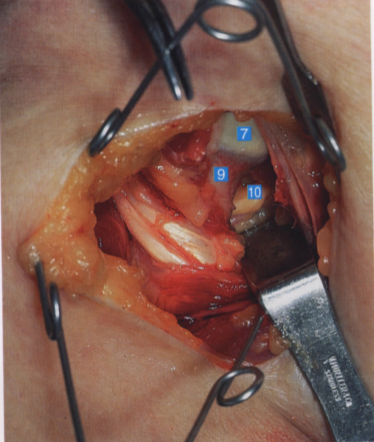

切开关节囊,显露出肱骨头及肩关节

1. 头静肌;2. 胸大肌;3. 三角肌;

4. 肱二头肌筋膜;5. 肱二头肌短头;

6. 肩胛下肌筋膜;7. 肱骨头;

8. 肩胛下肌和关节囊;9. 肱神经;10. 腋神经

肩胛下肌肌腱全部松解,腋神经从其后下缘经过